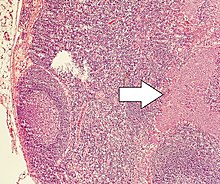

Small intestine neuroendocrine tumour high mag.jpg

Micrograph of a neuroendocrine tumor. H&E stain